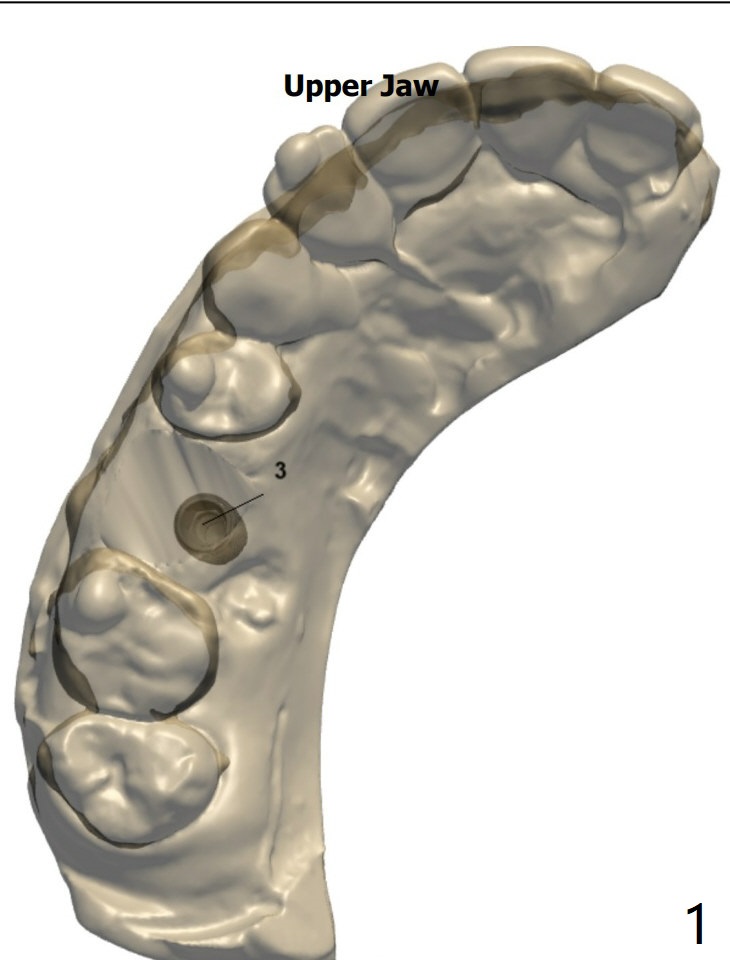

Diagnostic Treatment

A 53-year-old man with light lower lip paresthesia (unknown origin) finally agrees to treat #3 residual roots.